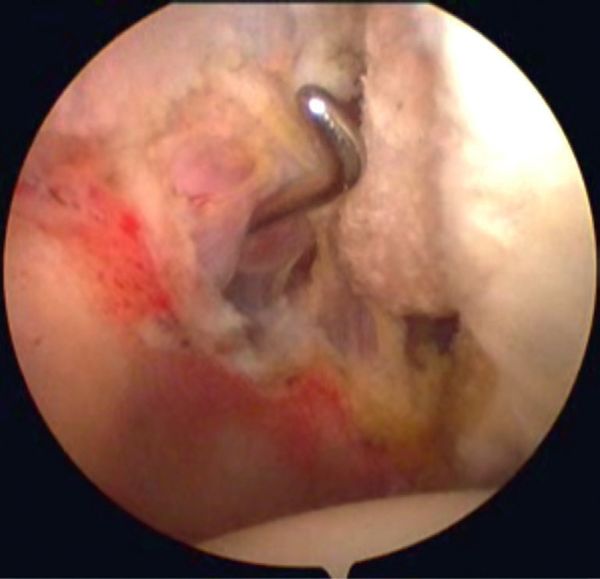

[[File:1562632306643-lg.jpg|center|thumb|600x600px|Figure. 6B Arthroscopic view (right shoulder) of a labral tear, elbow at side: confirming the medial pivot of the posterosuperior labrum around the posterosuperior glenoid rim.]] | [[File:1562632306643-lg.jpg|center|thumb|600x600px|Figure. 6B Arthroscopic view (right shoulder) of a labral tear, elbow at side: confirming the medial pivot of the posterosuperior labrum around the posterosuperior glenoid rim.]] | ||

This progressive avulsion is taken-up by Burkhart et al. as the aptly termed ‘peel-back mechanism’ observed by reproducing the cocking phase under arthroscopic control, confirming the medial pivot of the posterosuperior labrum around the posterosuperior glenoid rim (Figure and Video).

Peel-back mechanism